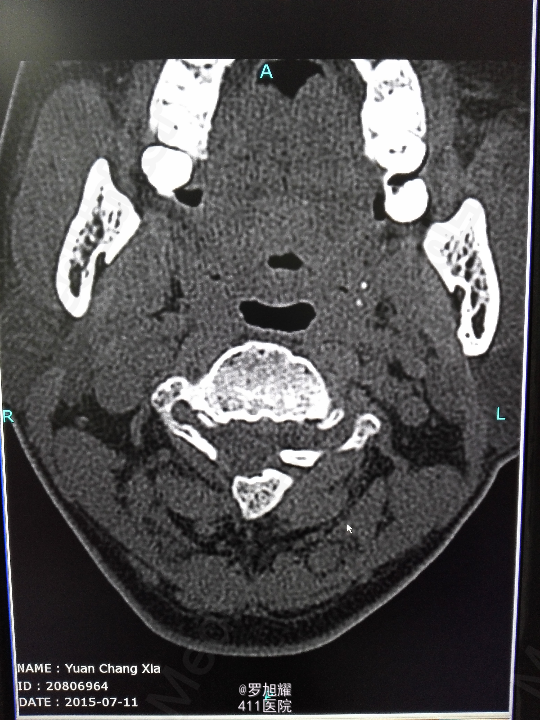

右侧躯体麻木1年,右上肢及下肢麻木2月余。 查体:颈椎活动受限,右上肢肘关节以远痛温觉减退,右侧胸4平面以下痛温觉及触觉减退,四肢肌力尚可,右侧霍夫曼征阳性,右侧上下肢所有腱反射亢进。 颈椎X线示:颈2椎板棘突缺如,颈3棘突肥大增高。 颈椎CT示:颈2椎板棘突缺如,颈3棘突肥大增高,颈2/3椎间盘突出,左侧颈2残留部分椎板进入椎管。枢椎齿突增生,寰枢关节退变。 颈椎MRI示:颈2/3椎间盘突出,左侧颈2椎板进入椎管,颈髓受压变性。

查体:颈椎活动受限,右上肢肘关节以远痛温觉减退,右侧胸4平面以下痛温觉及触觉减退,四肢肌力尚可,右侧霍夫曼征阳性,右侧上下肢所有腱反射亢进。 颈椎X线示:颈2椎板棘突缺如,颈3棘突肥大增高。 颈椎CT示:颈2椎板棘突缺如,颈3棘突肥大增高,颈2/3椎间盘突出,左侧颈2残留部分椎板进入椎管。枢椎齿突增生,寰枢关节退变。 颈椎MRI示:颈2/3椎间盘突出,左侧颈2椎板进入椎管,颈髓受压变性。